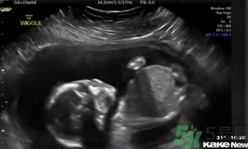

還只有5個(gè)月半的胎兒居然自己打自己的臉,這也太奇葩了,將來可能是個(gè)拳王啊。~美國(guó)堪薩斯州一個(gè)5個(gè)月半大的胎兒在母親子宮內(nèi)打自己的臉并把自己擊倒,這一幕剛好被父母用超聲波檢測(cè)儀記錄了下來,并被分享到網(wǎng)上,引得眾人稱奇。這對(duì)夫婦原本還擔(dān)心兒子可能會(huì)有腦震蕩,但護(hù)士讓他們放心。凡妮莎說,這次的事件導(dǎo)致他們開始考慮兒子的個(gè)性:“我們倆都愛終極格斗。所以我們正在討論他或許會(huì)成為一個(gè)拳擊手?!?/p>